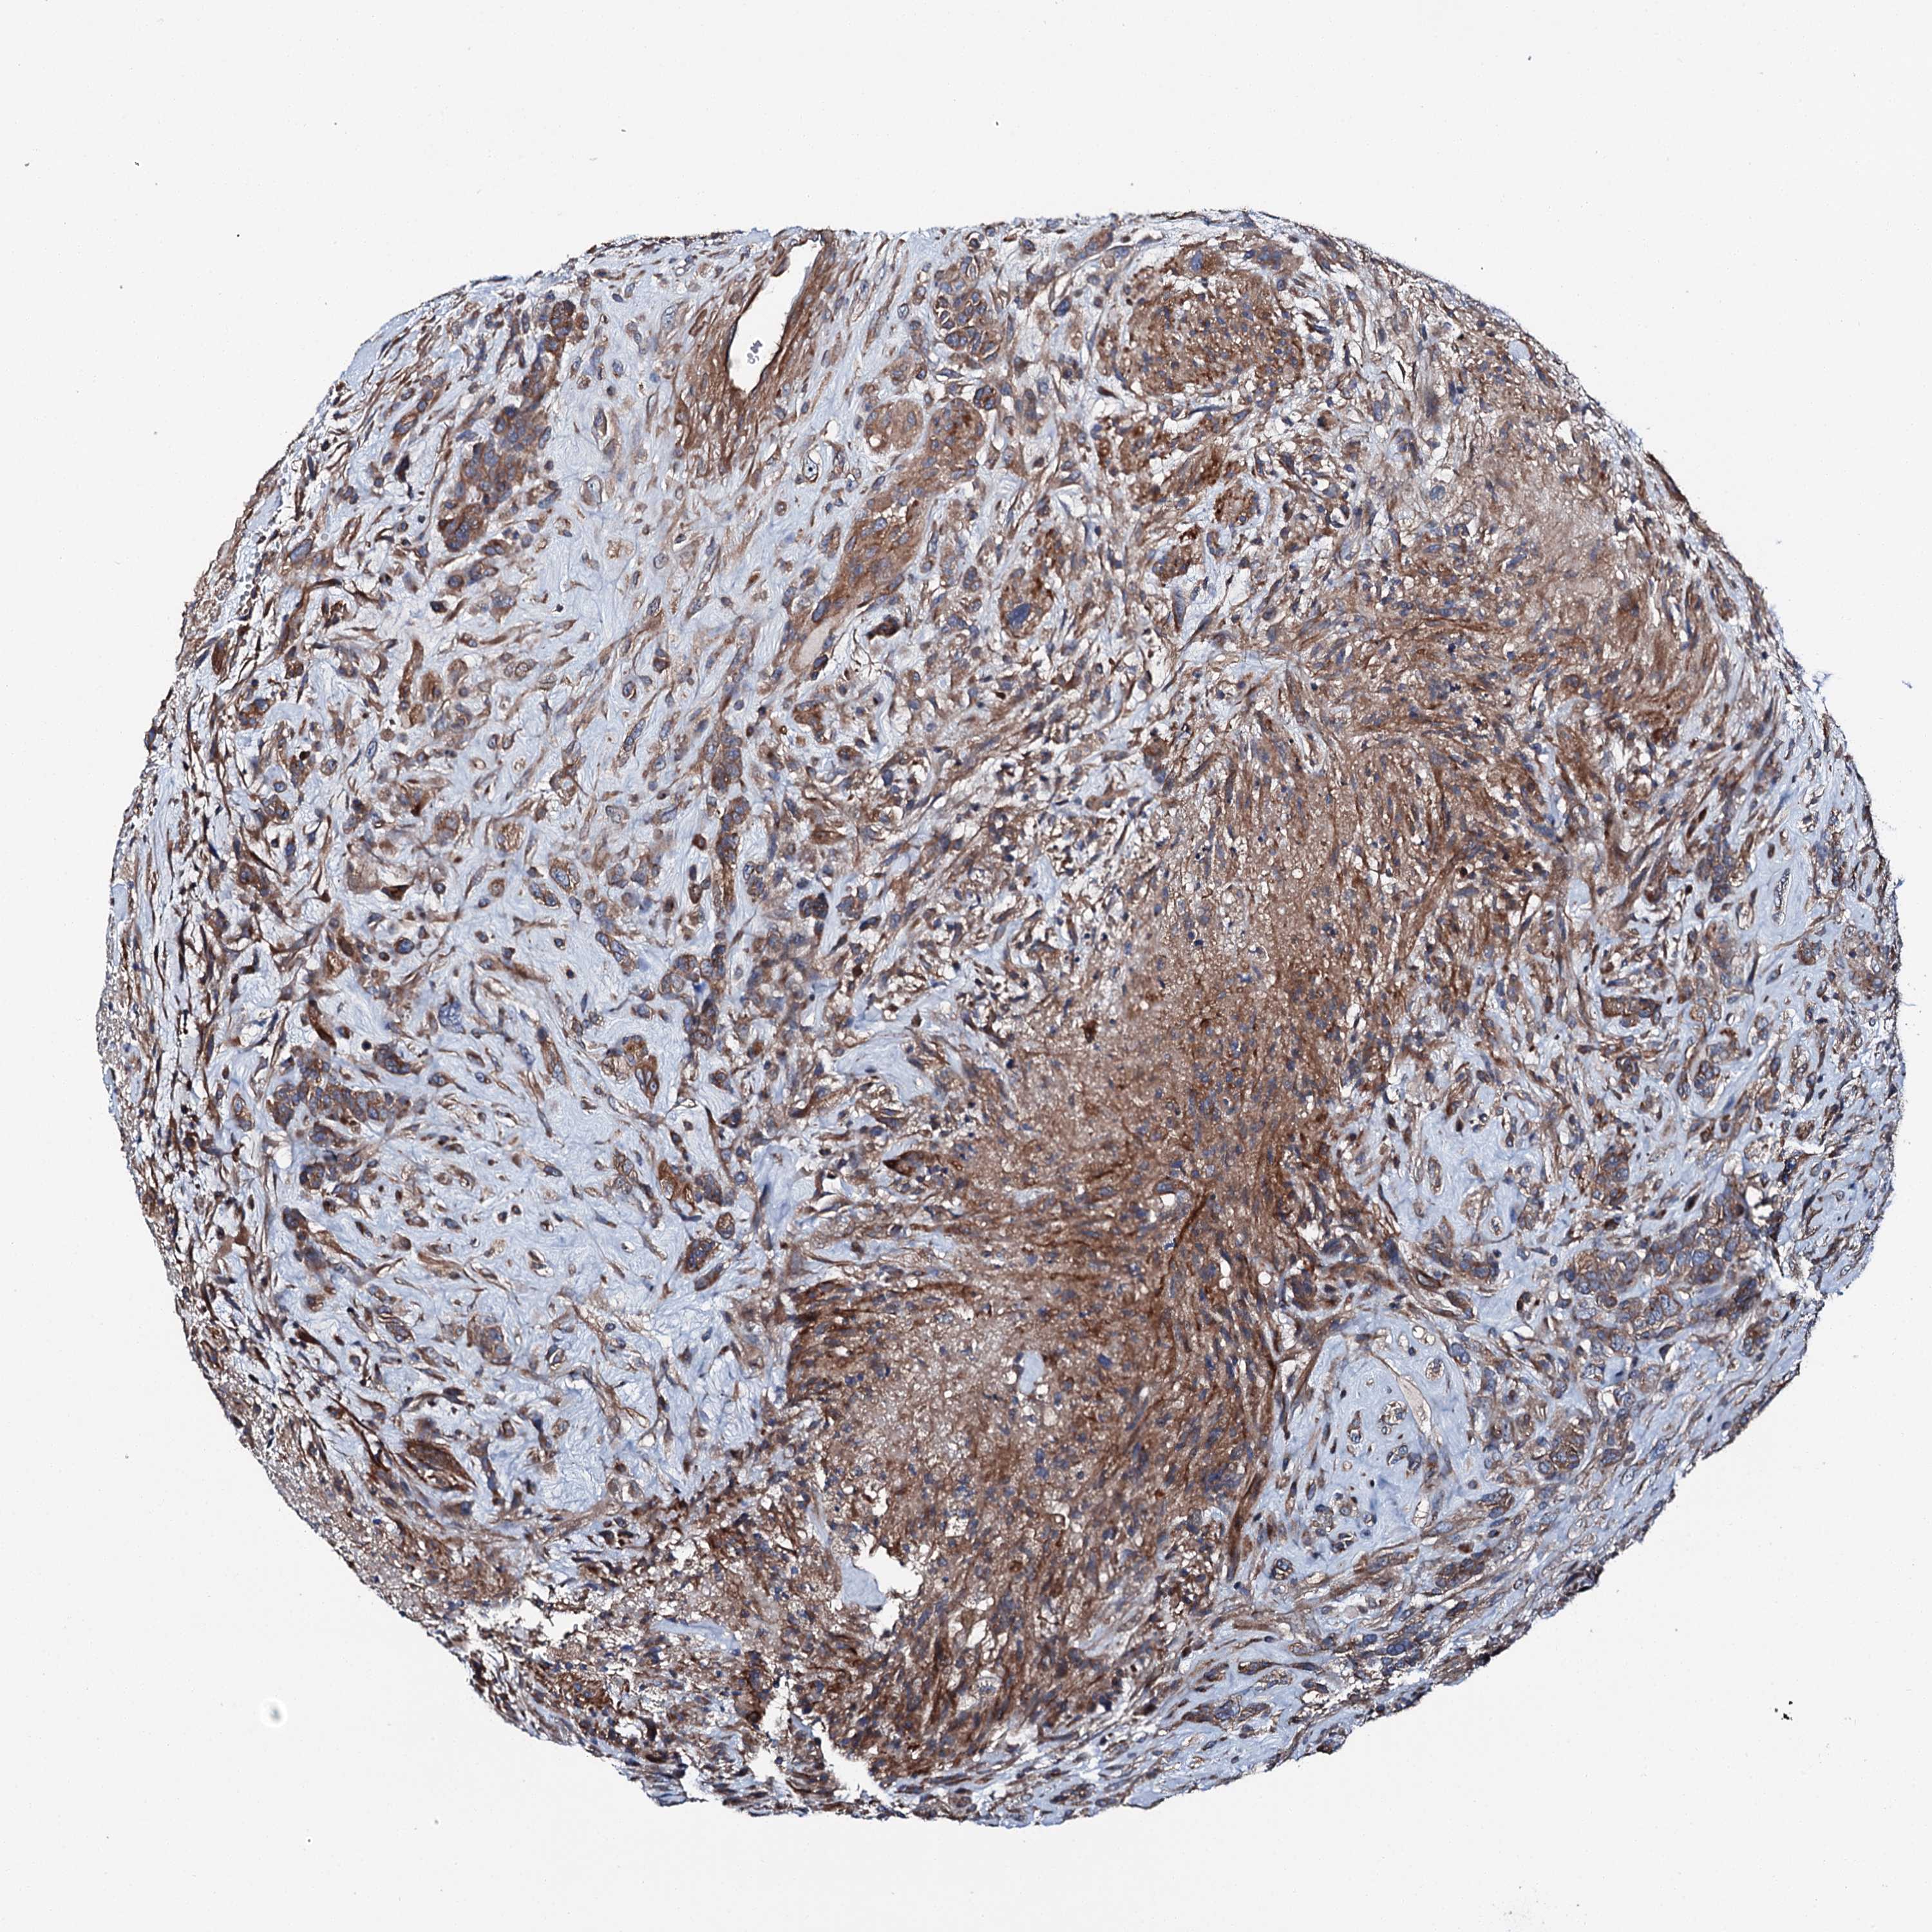

GLIOMA - Protein expressioni

A mouse-over function shows sample information and annotation data. Click on an image to view it in a full screen mode. Samples can be filtered based on level of antibody staining by selecting one or several of the following categories: high, medium, low and not detected. The assay and annotation is described here.

Note that samples used for immunohistochemistry by the Human Protein Atlas do not correspond to samples in the TCGA dataset.

Antibody stainingi

Antibody staining in the annotated cell types in the current human tissue is reported as not detected, low, medium, or high, based on conventional immunohistochemistry profiling in selected tissues. This score is based on the combination of the staining intensity and fraction of stained cells.

Each image is clickable and will lead to virtual microscopy that enables deeper exploration of all samples and also displays staining intensity scores, fraction scores and subcellular localization as well as patient and tissue information for each sample.

Antibody HPA039390

Staining

High

Medium

Low

Not detected

Intensity

Strong

Moderate

Weak

Negative

Quantity

>75%

75%-25%

<25%

None

Location

Nuclear

Cytoplasmic/membranous

Cytoplasmic/membranous,nuclear

Glioma, malignant, High grade

Glioma, malignant, Low grade